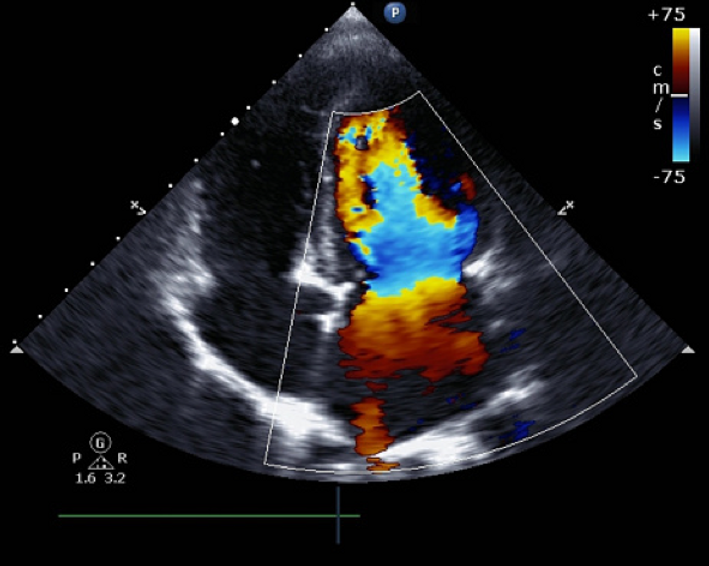

L’ecografia cardiaca, o ecocardiogramma, è un esame non invasivo che utilizza le onde sonore per creare immagini dettagliate del cuore. Questo permette ai medici di osservare la struttura e il funzionamento del cuore, inclusi le camere, le valvole e le pareti cardiache, così come il flusso del sangue attraverso il cuore.

È un esame cruciale per identificare patologie cardiache, anomalie strutturali, problemi alle valvole e altre condizioni cardiache.

La prevenzione è fondamentale quando si parla di salute cardiaca. L’ecocardiogramma gioca un ruolo vitale nel rilevare precocemente potenziali problemi cardiaci, permettendo interventi tempestivi che possono salvare vite o migliorare significativamente la qualità della vita dei pazienti. Questo esame è particolarmente utile per monitorare l’evoluzione di malattie cardiache note, valutare l’efficacia dei trattamenti e guidare le decisioni cliniche riguardo a interventi chirurgici o altre terapie.